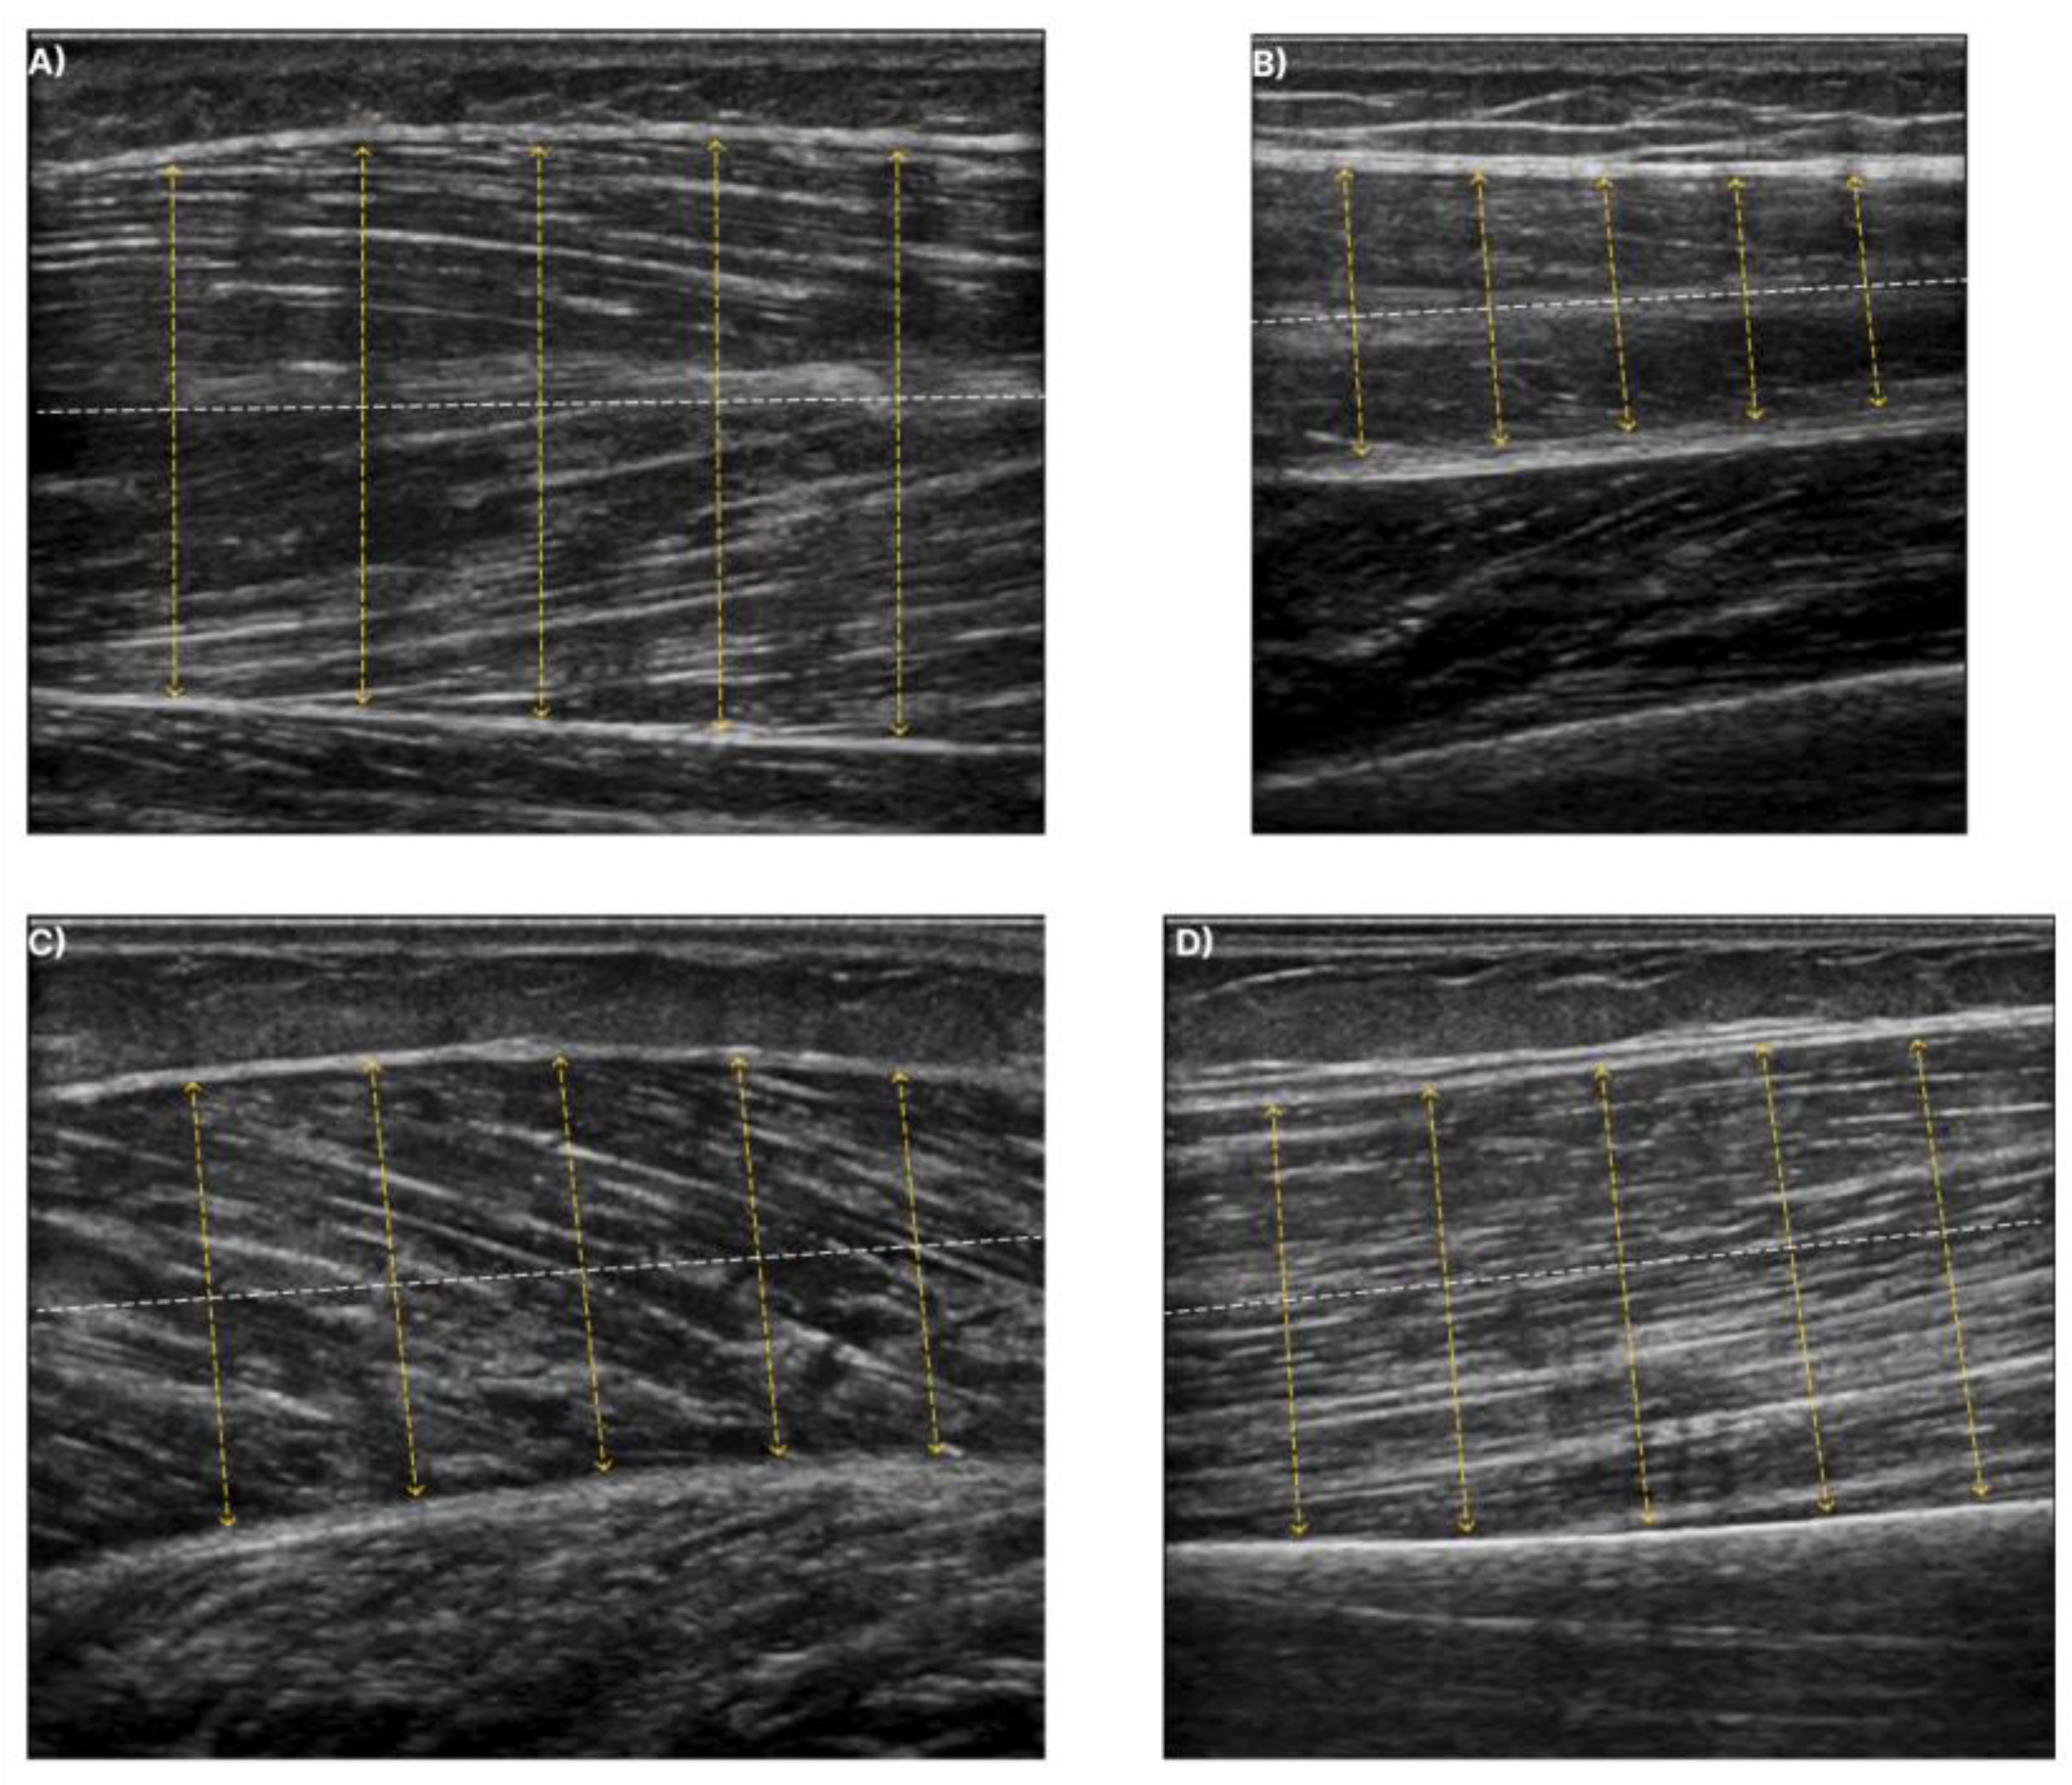

For training a deep learning model, annotated data pairs are required. Figure 4 depicts ultrasound images of the examined muscles along with their annotation. It must be mentioned that the annotation of the aponeuroses was performed with the guidelines of a specialised doctor. For improving the final performance, image augmentation techniques were incorporated. Rotation, scaling, vertical flipping, and random erasing were used. Regarding the optimization process, the weighted dice loss and an ADAM optimizer [35] were utilized along with a stepwise decrease in the learning rate as the learning rate policy. The input dimension of the deep learning models was 256 × 256 and lastly, the batch size was equal to 8 with 300 as number of epochs.

Figure 4. Ultrasound images for each muscle along with their corresponding annotation. The green structures in the annotation masks (second row) depict the deep and superficial aponeuroses. (A) shows T.A. muscle, (B) the R.F. muscle, (C) the GCM muscle, and finally (D) the B.B. muscle.